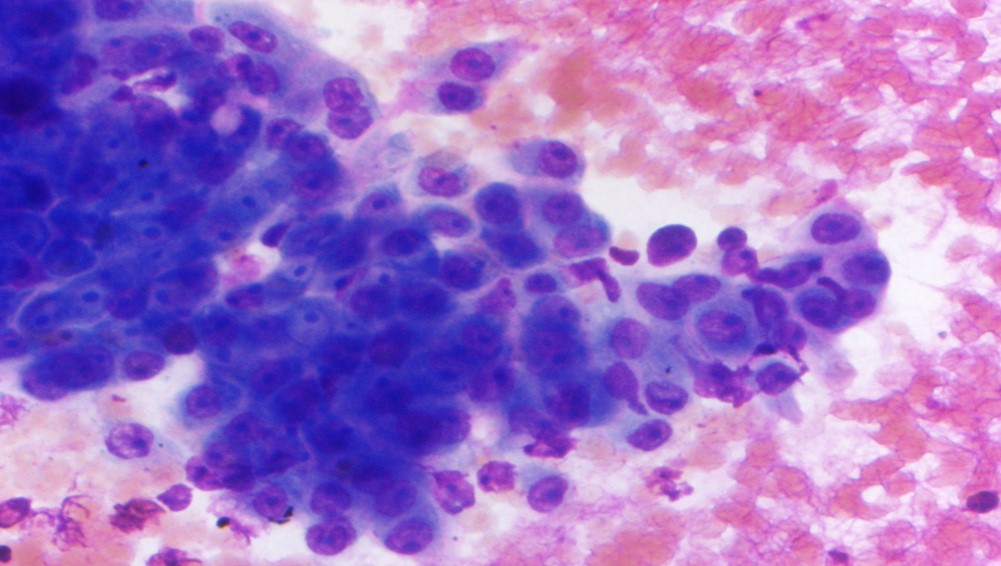

The specimen is cellular and consists of clusters and sheets of large atypical cells with macronucleoli and moderate amounts of somewhat dense cytoplasm. Occasional cells appear to have intracellular mucin and represent muciphages. Scattered benign ductal cells and acini are noted. Necrosis is absent. These findings are consistent with a high-grade salivary gland neoplasm, and a high-grade mucoepidermoid carcinoma is favored on cytology. Subsequent resection confirmed the cytomorphologic impression and showed also perineural invasion.

Mucoepidermoid carcinoma is the most common salivary gland malignancy in children and adults, and the most common malignancy of major and minor salivary glands. Low-grade tumors are more commonly cystic, while high-grade tumors are solid and infiltrative. The diagnostic feature is the combination of mucous cells, epidermoid/squamoid cells, and intermediate cells (which resemble squamous metaplastic cells). High-grade mucoepidermoid carcinomas have a greater proportion of squamoid cells with more cytologic atypia.